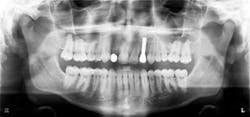

The following case study shows a Caucasian male, age 15 at the beginning of treatment. He had a peg lateral incisor No. 7 and was congenitally missing tooth No. 10. The treatment plan consisted of positioning tooth No. 7 for a veneer and opening space for an implant to replace tooth No. 10. After 30 months of orthodontic treatment had elapsed, there was still insufficient room for implant placement. There was sufficient room for the crown of No. 10, but the roots of teeth Nos. 9 and 11 were still too convergent to allow implant placement. The patient was leaving for college soon and was anxious to have treatment completed. The decision was made to have a periodontist do a corticotomy surgery to accelerate the tooth movement.

Corticotomy surgery was done and distal root movement was initiated on tooth No. 11 using a lever arm and elastic power chain. Root divergence was accomplished in eight weeks, and implant placement was accomplished at that time. The occlusion was detailed and orthodontic appliances were removed a short time later.